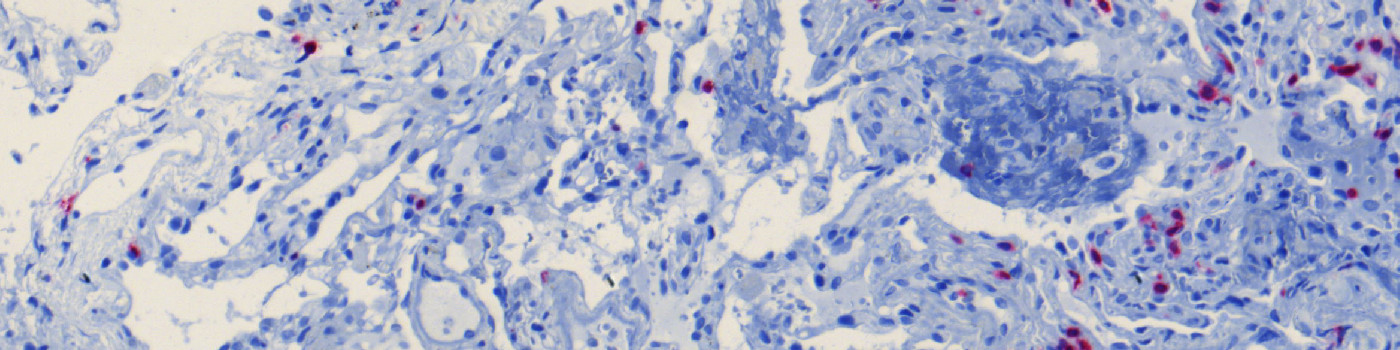

Figure 1

CD3 stained lung tissue.